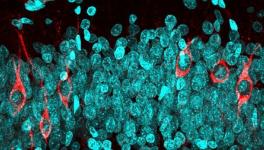

The corresponding author of the study, Willliam Seeley, a professor of neurology and pathology at the Memory and Ageing Centre and Weill Institute, has shown in his previous researches that brain atrophy in many forms of dementia is closely related to well-known brain networks. That is, group of functionally related brain regions that work cooperatively through their synaptic connections, sometimes even over long distances. In other words, these researches propose that instead of spreading evenly through the brain like that of a tumour, the neurodegenerative diseases jump from one part of the brain to another along the circuits that wire theses network together. The new study supports this idea.

The researchers began with the hypothesis that brain atrophy starts at some vulnerable region and then spreads out to anatomically connected regions via the synapses. They scanned brains of the patients to find out where the brain atrophy had begun. To do this, they built standardised maps of some 175 brain regions using FMRI (Functional Magnetic Resonance Imaging) of 75 healthy persons. They then matched these standardised maps with the scans from FTD affected people and found out the hub of the brain atrophy as the likely epicentre of the patient’s degeneration.